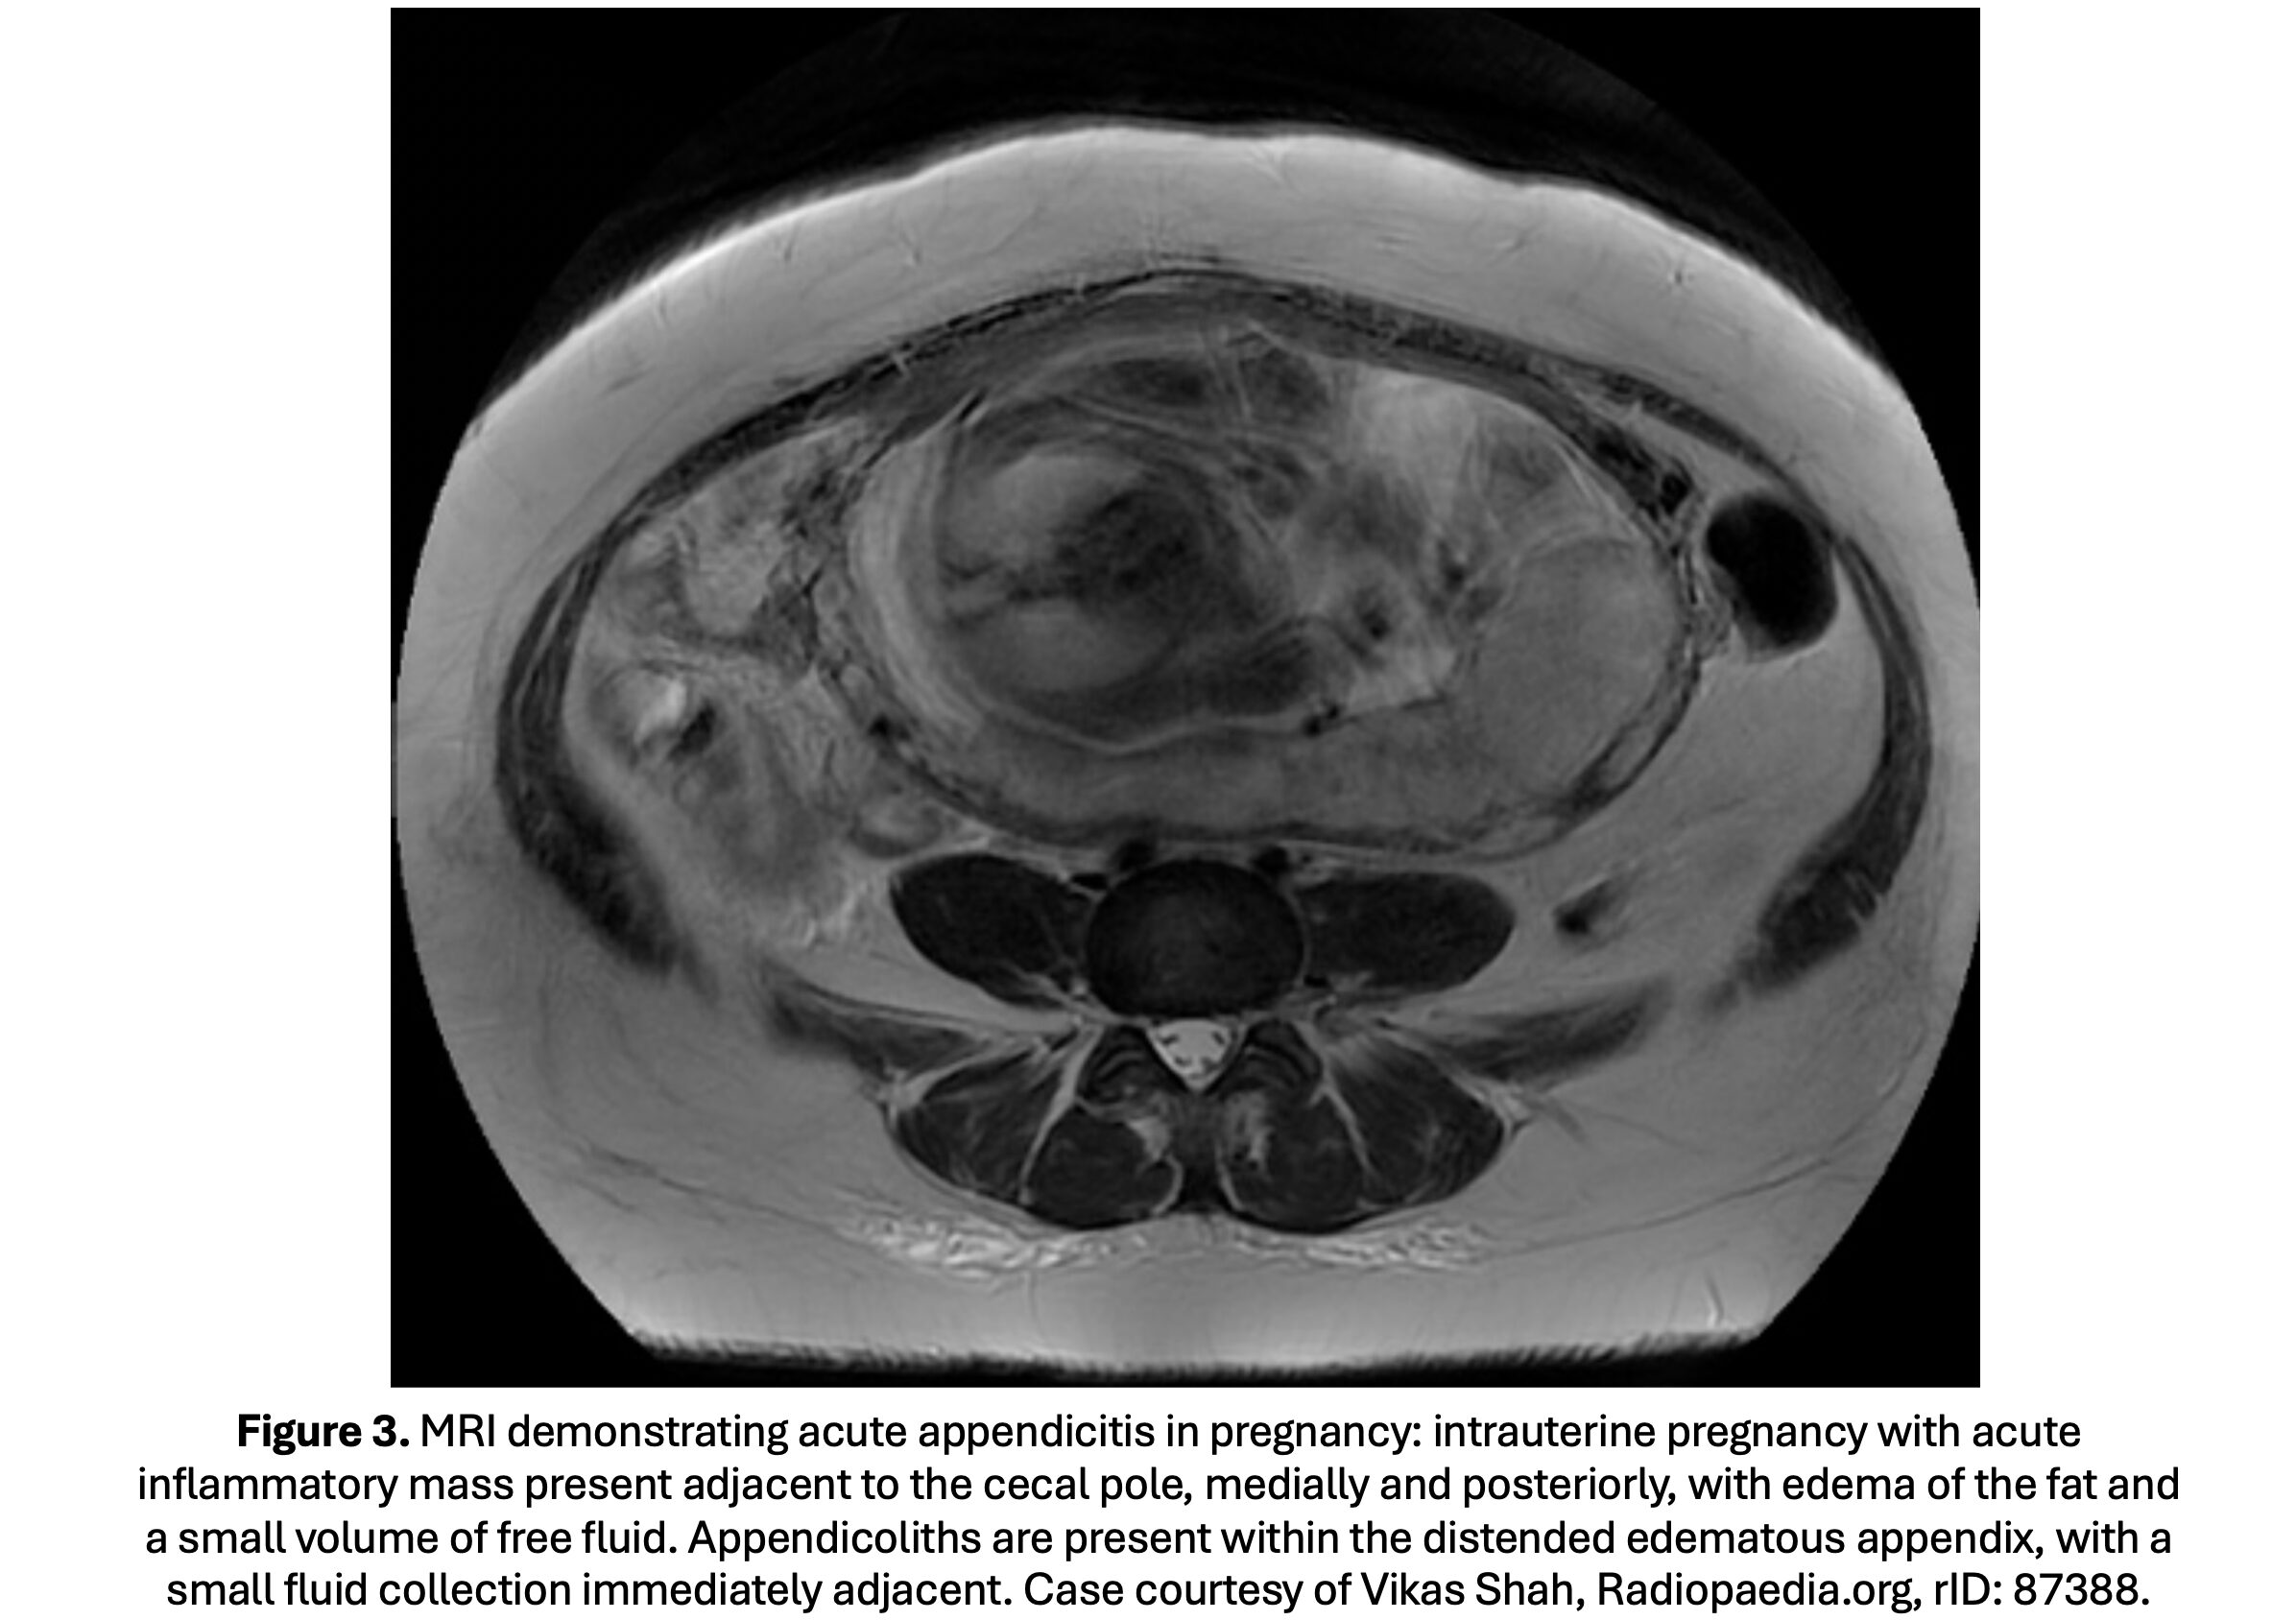

- This test is mostly used in pregnant women if US is unavailable or equivocal; MRI can also be used as a first-line imaging modality if available (61,62).

- Sensitivity is 85-98% and specificity is 97-99% for experienced radiologists; lower in less experienced readers (77-89% and 79-83%, respectively) (63-69).

- In pregnant patients, sensitivity ranges between 89-100% and specificity 93-99% (70-75).

- MRI findings: fluid-filled, enlarged appendix (>7 mm) (Figure 3).